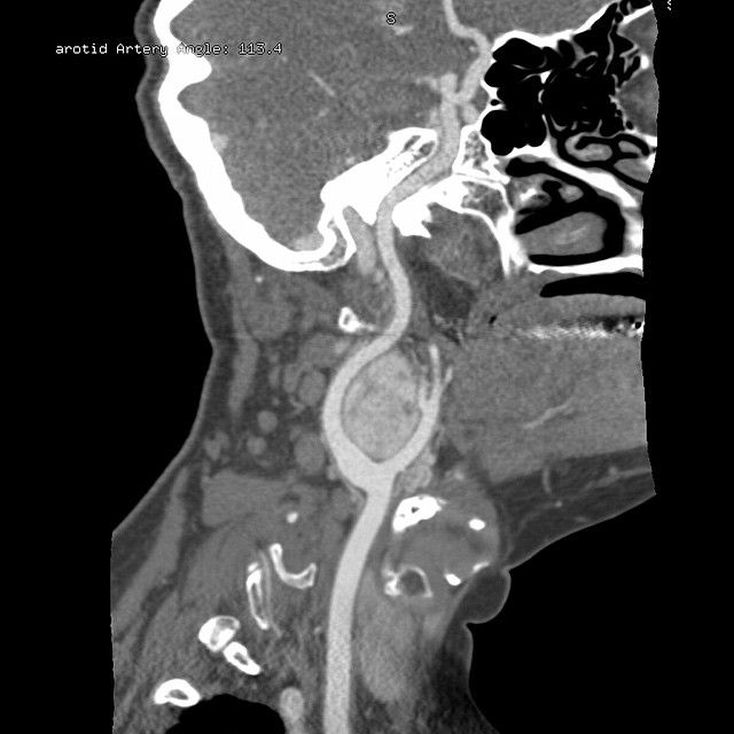

This curved reformat of a CT angiogram shows an arterial-phase enhancing lesion located between the internal and external carotid arteries. This is a typical location and appearance of a carotid body tumour (also known as carotid body paraganglioma). It is a highly vascular glomus tumour that arises from the paraganglion cells of the carotid body. Carotid body tumours are the most common type of paraganglioma of the head & neck, with the most common location being the carotid bifurcation. Malignant features may be seen in 6% of head & neck paragangliomas. Surgical excision is the treatment of choice. The larger the tumour the higher the risk of operative complications, which may require radiotherapy.